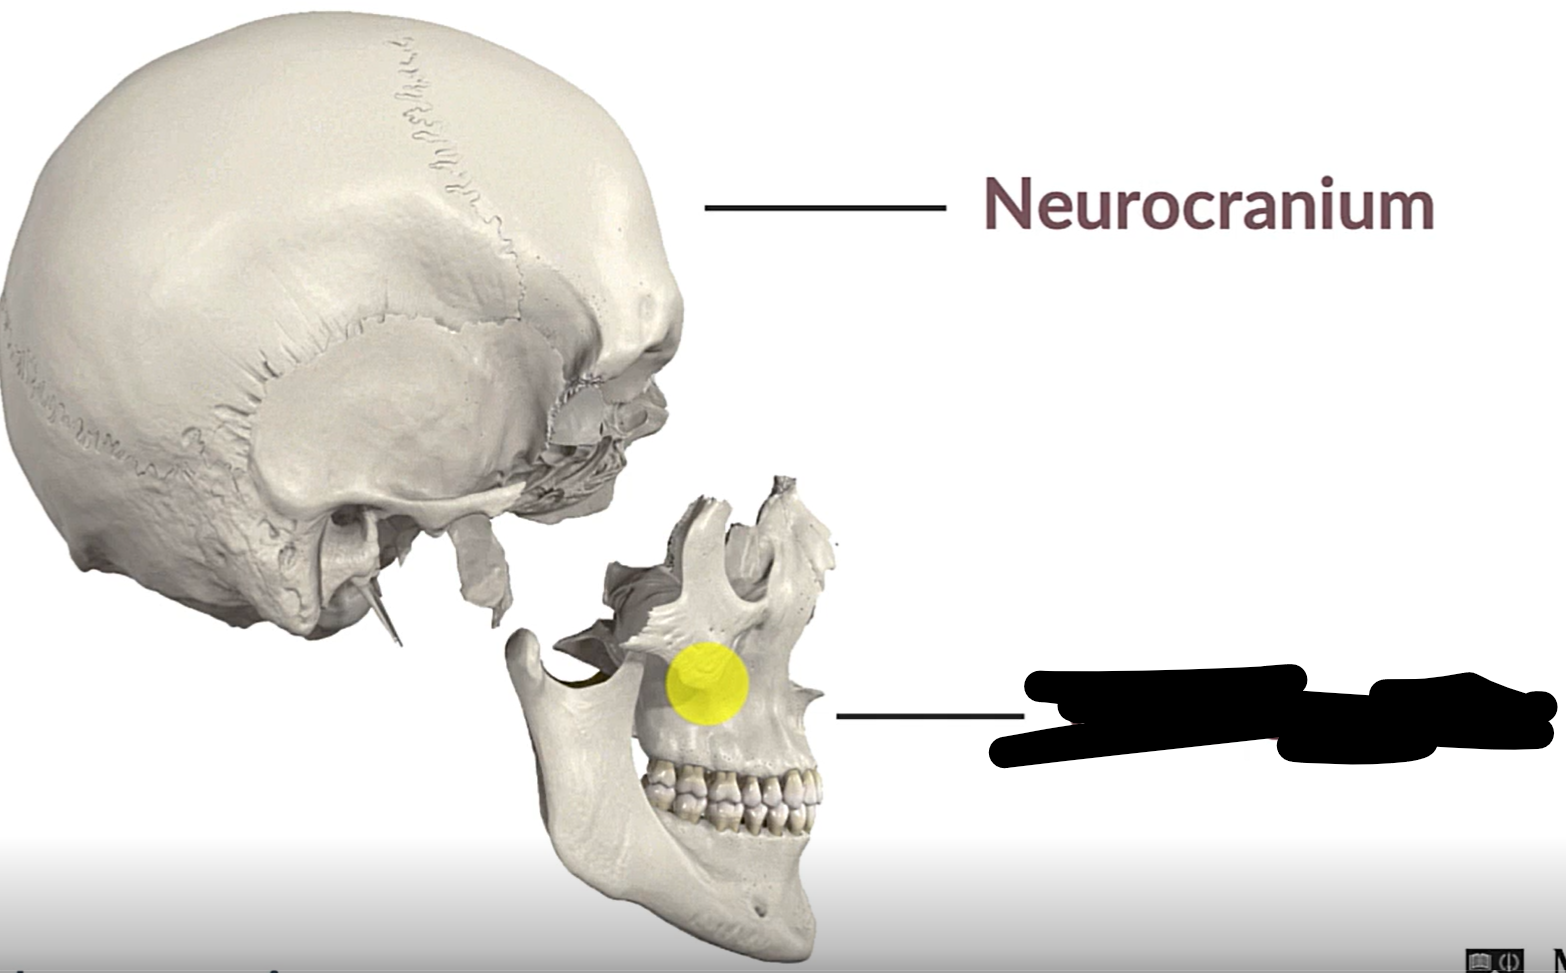

Neurocranium

Viscerocranium

What bones make up the neurocranium?

Occipital bone (1)

Parietal bones (2)

Frontal bone (1)

Temporal bones (2)

Sphenoid (1)

Ethmoid (1)